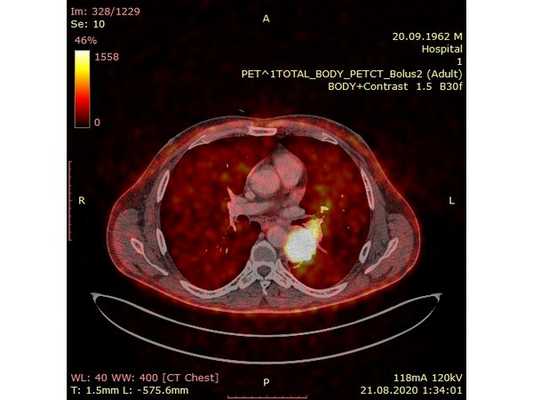

31.07.2020 мужчина 57 лет обратился в Клиническую больницу № 2 АО ГК МЕДСИ с данными компьютерной томографии, где выявлено центральное новообразование в корне нижней доли левого лёгкого.

Чтобы провести первичное стадирование опухоли, пациенту проведена позитронно-эмиссионная томография в сочетании с компьютерной томографией (ПЭТ-КТ). По данным исследования, выявлена метаболически активная опухоль в корне левого лёгкого с бугристыми контурами размерами 41 х 43 мм. В толще опухоли проходят нижнедолевой бронх и бронх 6-го сегмента левого лёгкого, просветы бронхов значительно сужены. Нижняя доля левого лёгкого уменьшена в размерах за счёт того, что сегменты 6, 9 и 10 субтотально (частично) инфильтрированы и безвоздушны. Лимфатические узлы корня лёгкого и средостения не увеличены в размерах и не накапливают радиофармпрепарат (РФП), который был введён пациенту перед обследованием внутривенно. Других очаговых образований и очагов гиперметаболизма в организме не обнаружено.

При этом отмечено, что опухоль распространяется в средостение по нижней стенке левого главного бронха и широко прилежит к нижнегрудному отделу аорты (по заключению специалиста ПЭТ-КТ — имеется инвазия опухоли в ткани средостения и возможное врастание в стенку аорты). При самостоятельном пересмотре изображений отмечено, что "опухолевая" ткань, которая распространяется по нижней стенке левого главного бронха в средостение, не накапливает РФП (т. е. не является злокачественной), а стенка аорты в области "инвазии" опухоли имеет ровный чёткий контур и адвентициальную границу, что также свидетельствует об отсутствии онкологического процесса в этой области.